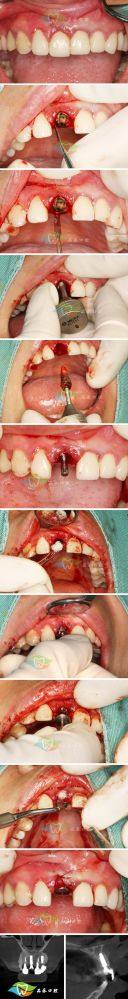

1. 牙齿拔除后即刻种植:这是何思铃医生非常擅长的项目之一。当患者的牙齿需要拔除时,传统的方法可能需要等待一段时间后再进行种植,而即刻种植则可以在拔牙后立即进行。这样可以减少患者的就诊次数和等待时间,同时也能更好地保存牙槽骨的形态和质量。何医生在这个项目上有着丰富的经验,能够精细地把握种植的时机和位置,确保种植体的稳定性和成功几率。

2. 微创种植:微创种植是一种精良的种植技术,它通过微小的切口将种植体植入牙槽骨内,减少了手术的创伤和疼痛,术后修复也更快。何医生熟练掌握这种技术,能够在确保种植成效的前提下,较大程度地减轻患者的痛苦。在手术过程中,她会运用精细的操作和精良的设备,确保种植过程顺利进行。

3. 前牙美学区种植及修复:前牙的美观对于患者的形象非常重要。何医生在这个领域有着独特的见解和丰富的经验。她能够根据患者的口腔情况和面部特征,设计出更适合的种植方案,使种植后的牙齿不仅功能良好,而且在外观上与天然牙齿几乎无差异。在修复过程中,她会选用高质量的修复材料,确保修复成效的持久性和美观性。